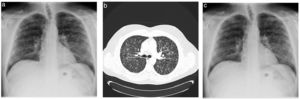

The patient was a 45-year-old man who was an active smoker and had no significant personal history. He consulted for constitutional symptoms, dyspnoea and two-month history of dry cough. A bilateral micronodular pattern respecting costophrenic angles was observed in the chest radiograph (Fig. 1A). Based on these findings, the study was expanded to include computed tomography (CT) of the chest. The CT scan revealed an interstitial pattern with heterogeneous microcystic changes in the upper lobes and also small centrilobular nodules that may cavitate, known as the Cheerio sign (Fig. 1B). Subsequently, a bronchoscopy was performed for bronchoalveolar lavage and transbronchial biopsy. The immunohistochemistry results showed CD45 and CD1 at less than 5%.

Despite the initial negative results, but high suspicion of histiocytosis, a surgical biopsy was requested, which revealed pulmonary Langerhans cell histiocytosis (PLCH).

PLCH is a rare interstitial disease that occurs in young adults and accounts for 3–5% of all adult diffuse lung diseases.1 This case is considered relevant because the diagnosis was made despite the negative immunochemistry results.

It is important to recognise this characteristic sign in the differential diagnosis of lung adenocarcinoma and metastasis or fungal, mycobacterial or rheumatoid nodules.2,3 This is because the therapeutic management of this condition is entirely different and early diagnosis can lead to a rapid recovery without medical treatment, as in our case with smoking cessation (Fig. 1C)